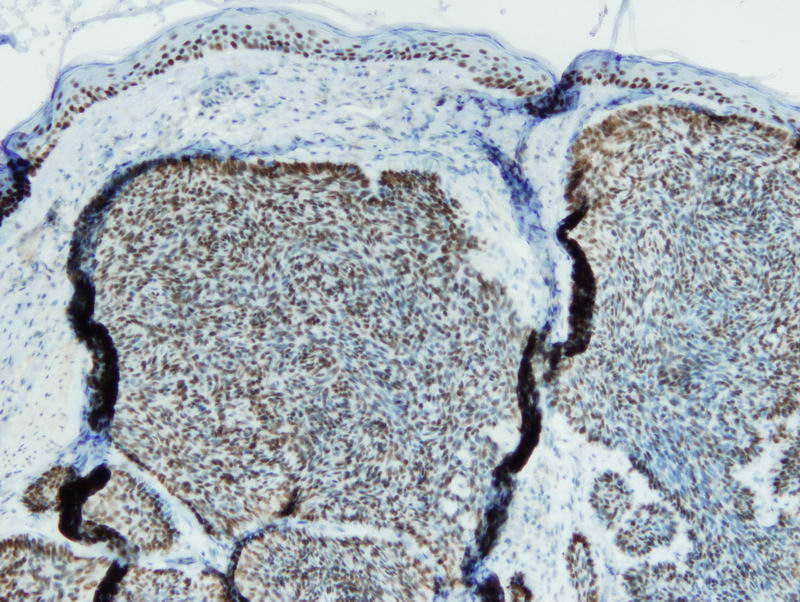

Anti-p63

Rabbit clonal antibody

Product ID:DB 134 Category:IHC-P

IHC-P, dilution 1:100

Gallery

db134a db134b db134c db134d